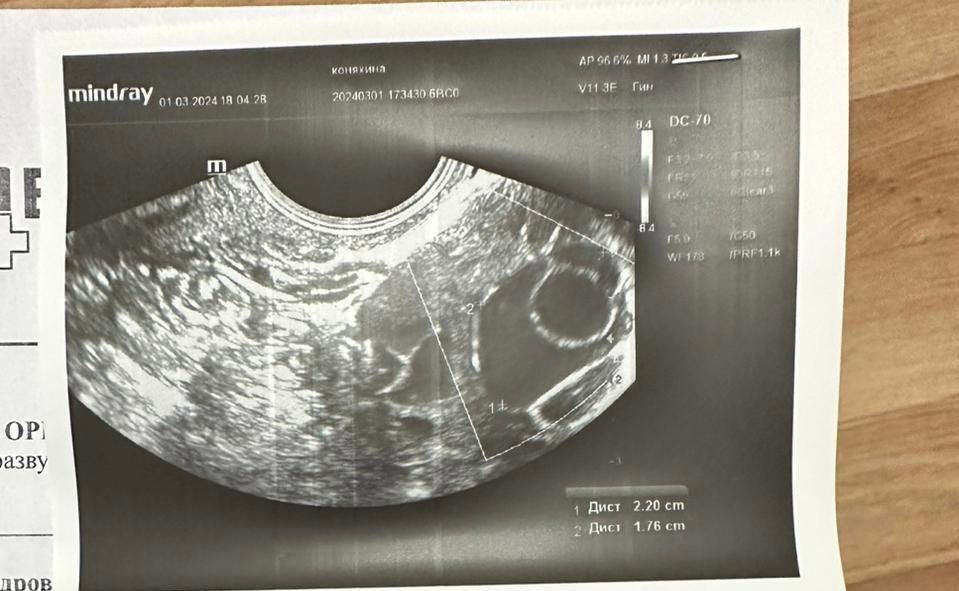

Пошла второй раз на узи 6.03, но в другую клинику и врачу, жт нет…(второе фото) куда оно делось? Может его просто не увидели?

Алина, 30 дц, но на это не стоит в моем случае ориентироваться, у меня спкя и своей овуляции нет, у меня была стимуляция, на которой сначала не было ответа, потом добавили еще препарат и вот типа овуляция произошла. Сегодня якобы 7-8 дпо

Елизавета Коняхина, я думаю это ДФ у вас был а не ЖТ. И овуляция возможно произошла перед тем как вы во второй раз на УЗИ ходили (фолликул лопнул и ЖТ не успело образоваться ещё). За 8 дней с 27.02 как раз ДФ должен был вырасти с 10 мм до 23-26мм и лопнуть. Но возможно и регрессировал ДФ без овуляции. Жидкости свободной не было на втором УЗИ?